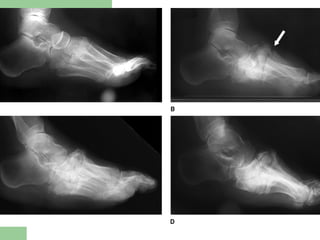

Radiographic Staging

(Eichenholtz, 1966)

 I Developmental (acute) stage

 II Coalescence (quiescent) stage

 III Consolidation (resolution) stage

Radiographs

 Stage I

 Stage II

 Stage III